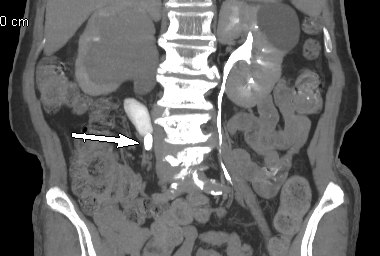

余婆婆腹中的腎結(jié)石